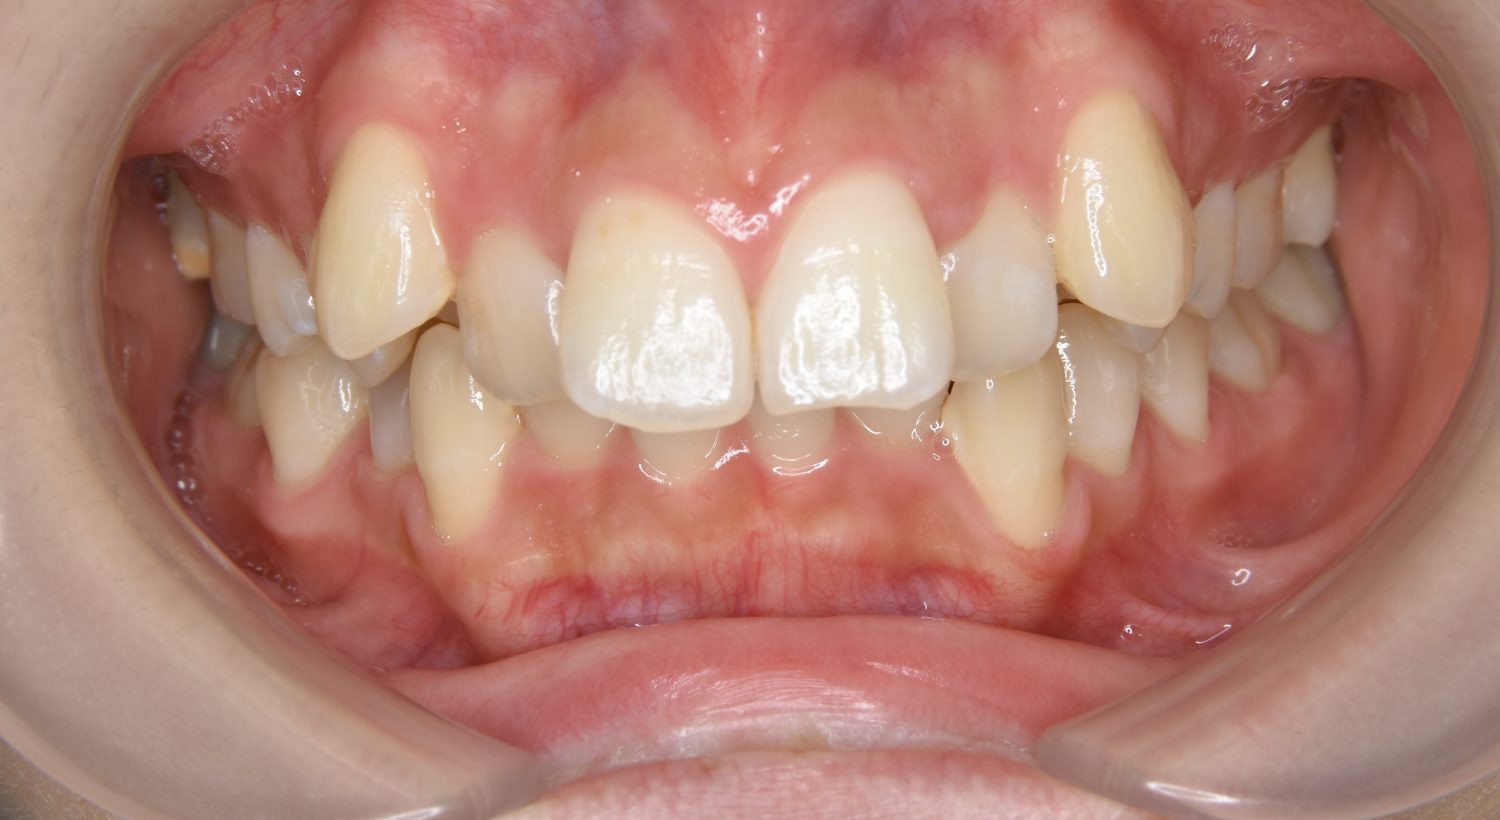

叢生の症例紹介②

Before

After

主訴

歯の凸凹を治したい。

治療内容

アライナー(インビザライン)にて非抜歯で治療を行いました。

治療費

1,150,000 円(税込)

治療期間

26ヶ月

通院回数

14回

想定されたリスク

※歯根吸収、歯肉退縮、歯髄壊死、顎関節症状

※アライナー(インビザライン)は日本の薬機法未承認の矯正装置であり、医薬品副作用被害救済制度の対象外となる場合があります。

丸山和宏先生

ピーススマイル矯正歯科

上下前歯部に叢生(凸凹)が認められる状態でした。歯列の遠心移動を行うことで機能面および審美面が改善されました。